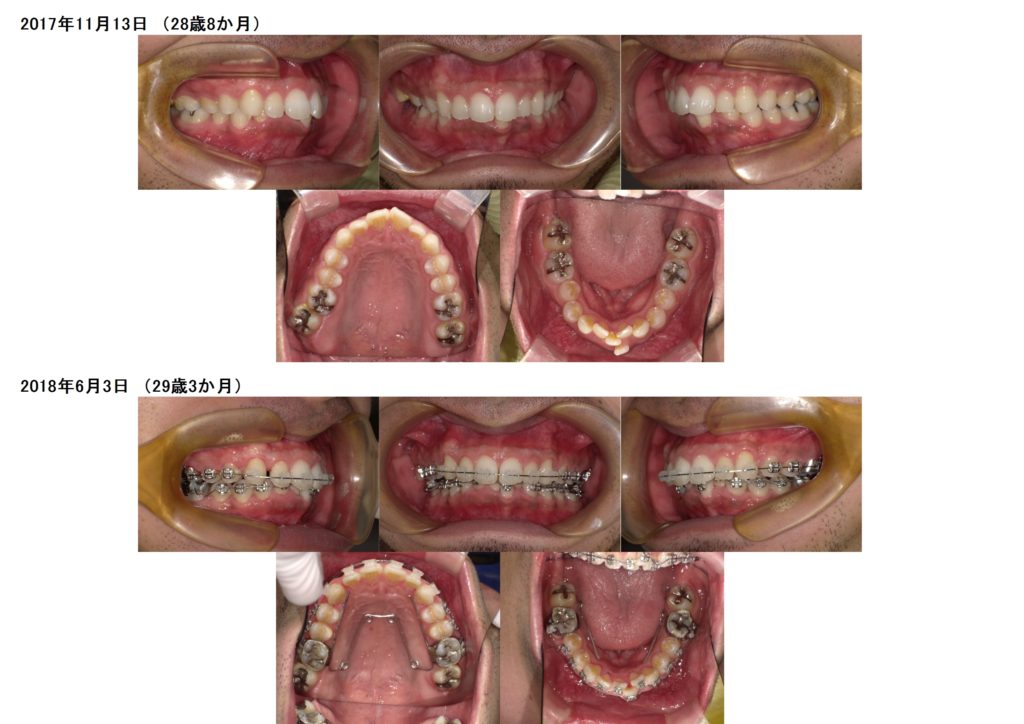

お口元が出ているのと、下の歯並びが気になるという事で、治療を開始しました。

上下の口腔内写真を見比べていただくと、約半年ほどで下のガタガタしていた歯並びが徐々に治っているのが分かると思います。

初めは本当にお口の中も大変だったと思いますが、キレイに歯ブラシもしてバッチリ☆

そこからさらに5か月ぐらいでガタガタは改善され、噛み合わせの調整に入りました。